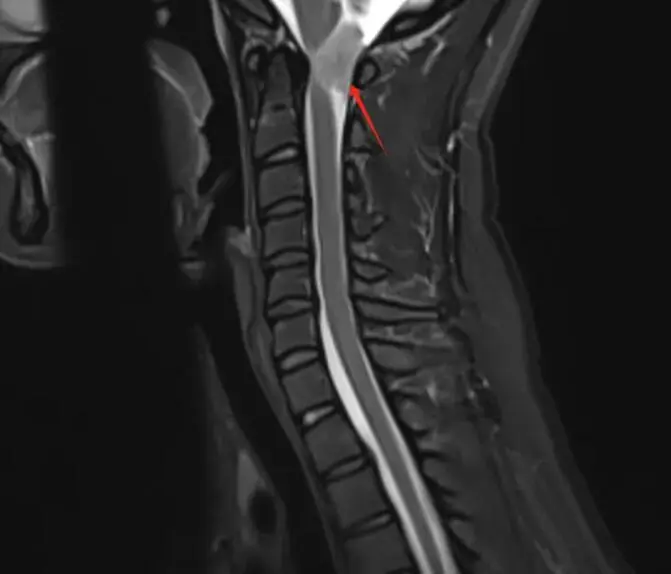

林女士,40岁,左侧头颈部疼痛1年,一直以为只是偏头痛,药物治疗,但效果甚微。后来到我中心做了头颅磁共振平扫;颈椎磁共振平扫+增强,终于发现症结所在。

磁共振图像

T1压脂平扫

检查所见:检查发现其C1椎体-向上枕大孔上部水平椎管髓外硬膜下占位,考虑是脊膜瘤。

T1WI多为等信号或低信号,T2WI多为等信号或稍高信号,钙化显著时信号不均质;增强扫描多呈明显均匀强化,部分可见特征性的“硬膜尾征。